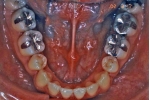

マルチブラケット終了時

|